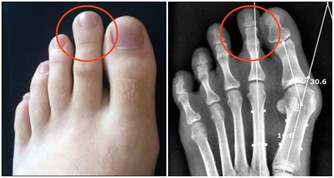

中老年人,尤其是女性,眼瞼上新出現黃色、橘色或者棕紅色斑塊或者結節,不痛不癢,就很可能是黃色瘤。

這瘤經常長在上眼瞼的內眼角處,也可能出現在臉部其他部位或膝蓋上,針頭或黃豆大小,邊緣略高出皮膚表面,質地較柔軟。